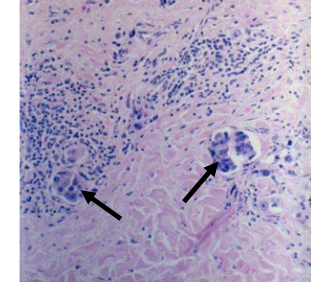

medullary carcinoma micrscopy

syncytial growth pattern

high nuclear grade

lymphoplasmacytic infiltrate

pushing, nonifiltrative border

ugly cells oftenin sheets